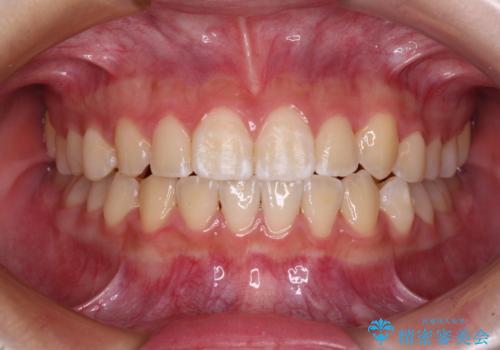

前歯のすきっ歯を治したい インビザラインによる矯正治療

- 上顎前歯の隙間を気にして来院された患者様です。

目立たない装置を希望とのことで、インビザラインを用いて矯正治療を行うこととしました。

一度インビザラインのマウスピースセットをお渡しすると1年以上来院されず、マウスピースを破損したり紛失したりすると来院されるというのんびりとしたペースで治療を行ったため、4年間という長期にわたる治療となりました。

最終的には隙間は全て閉じ、綺麗な仕上がりとなりました。